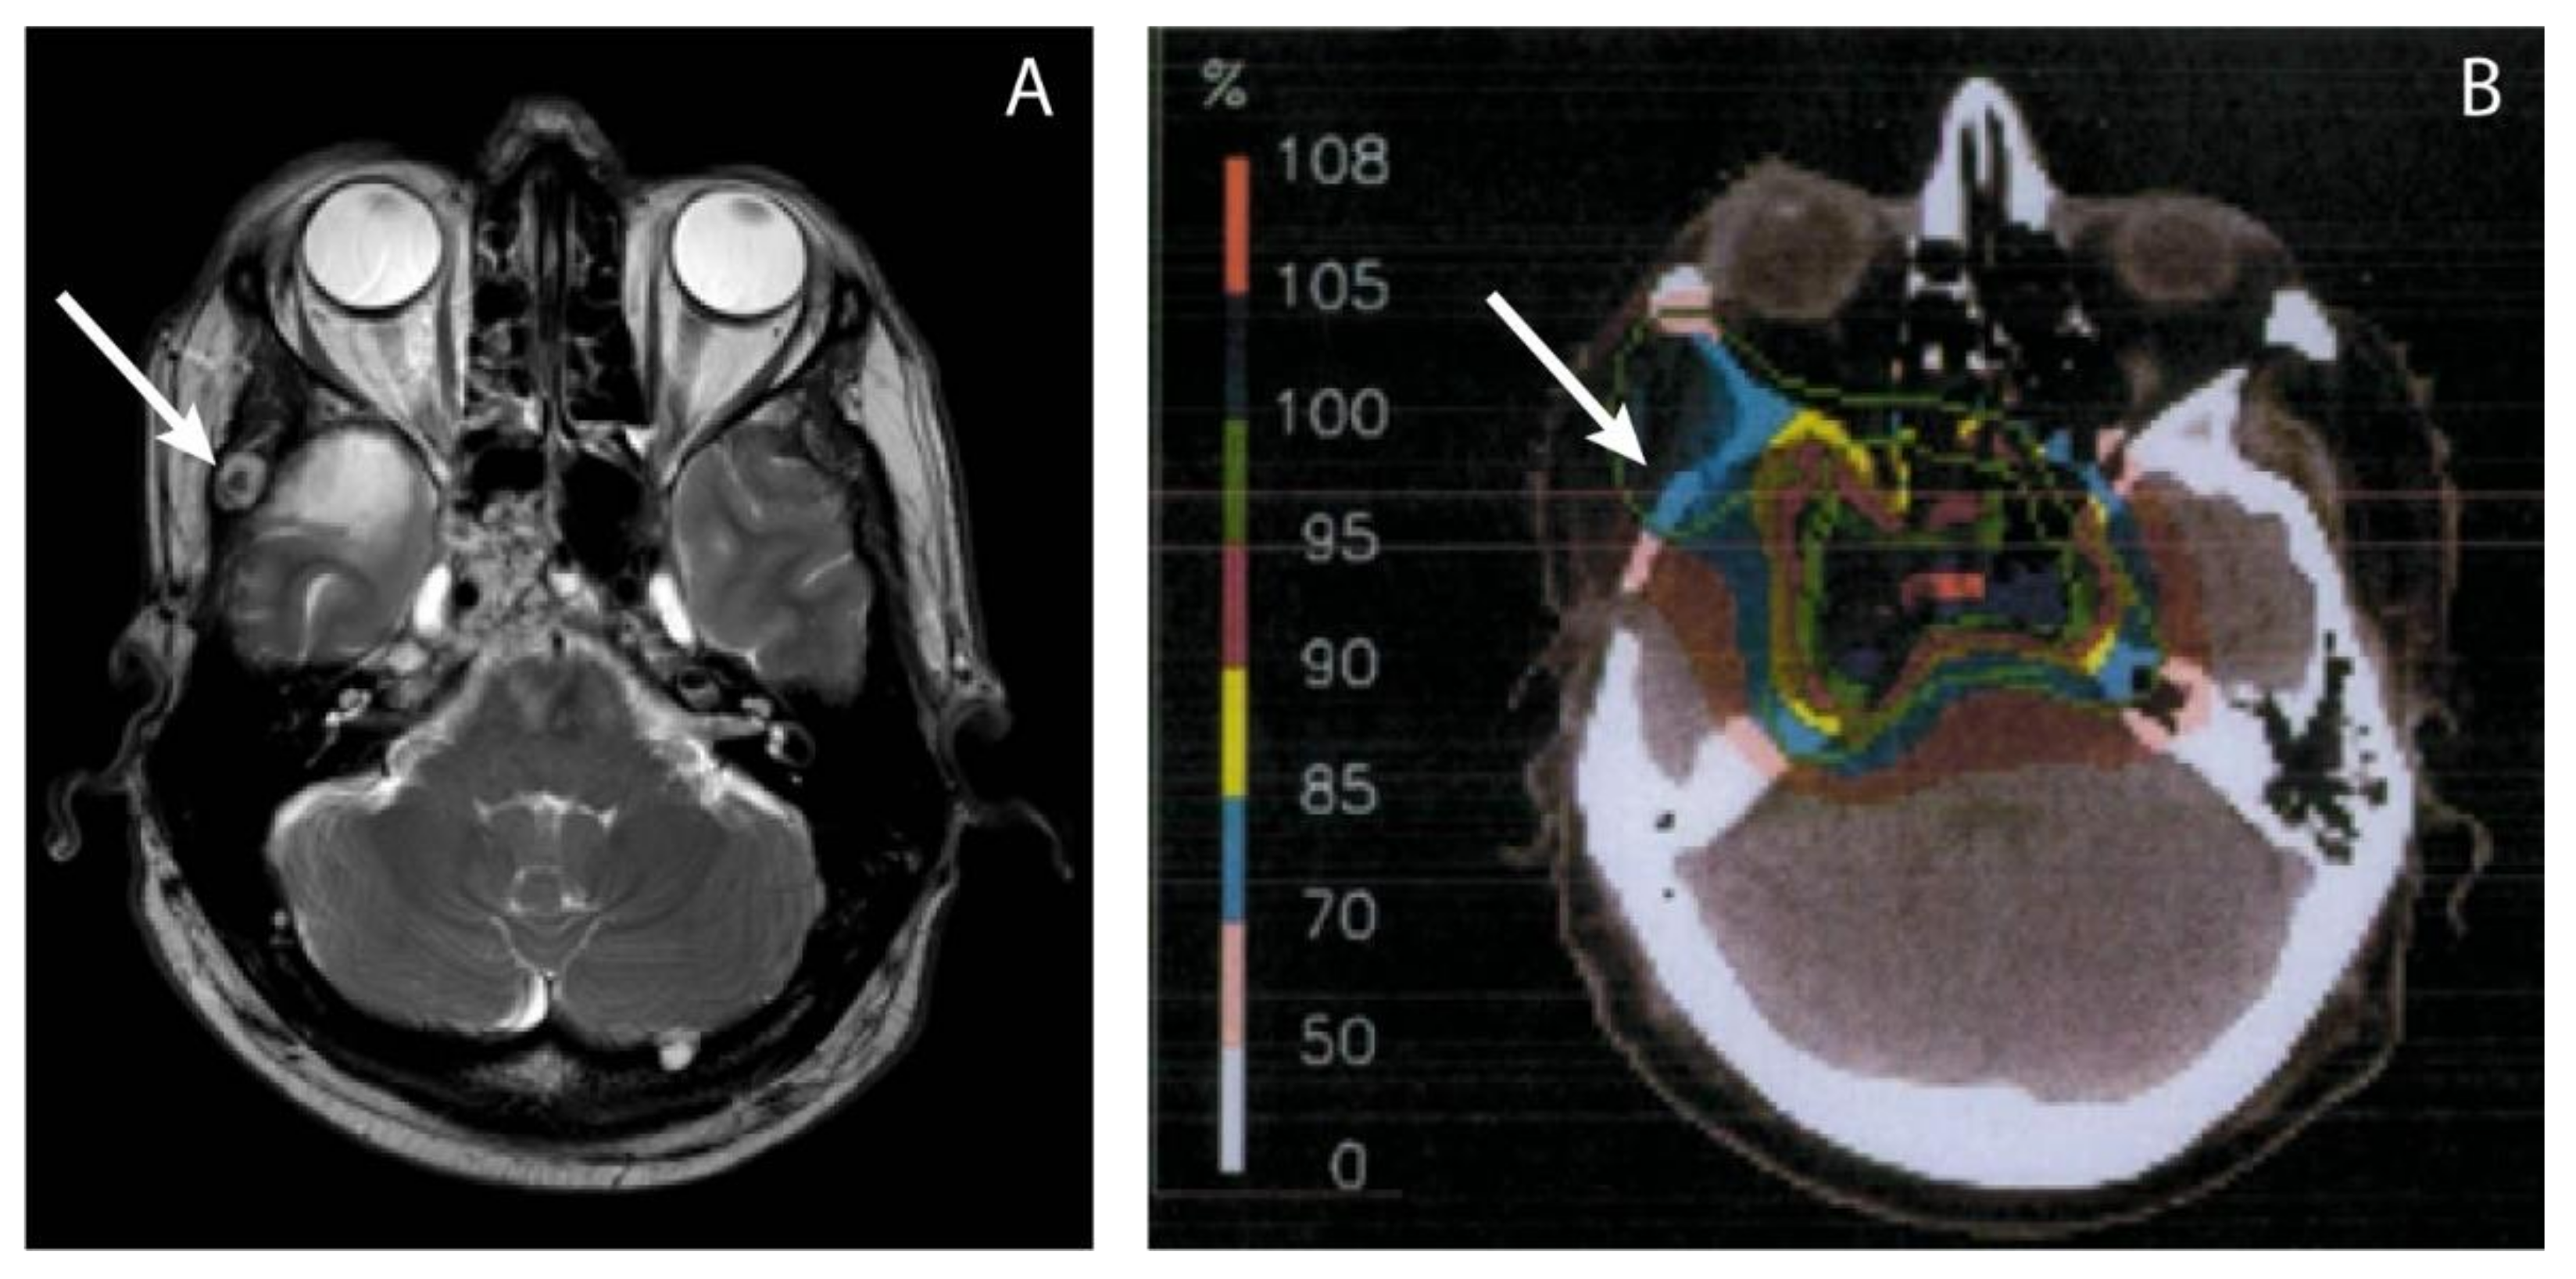

| 3 | Craniocervical junction |

| Proton | Subcutaneous retroauricular Subcutaneous neck 3x Neck muscle left + right | 18 | Surgery Photon radiotherapy (Linac) |